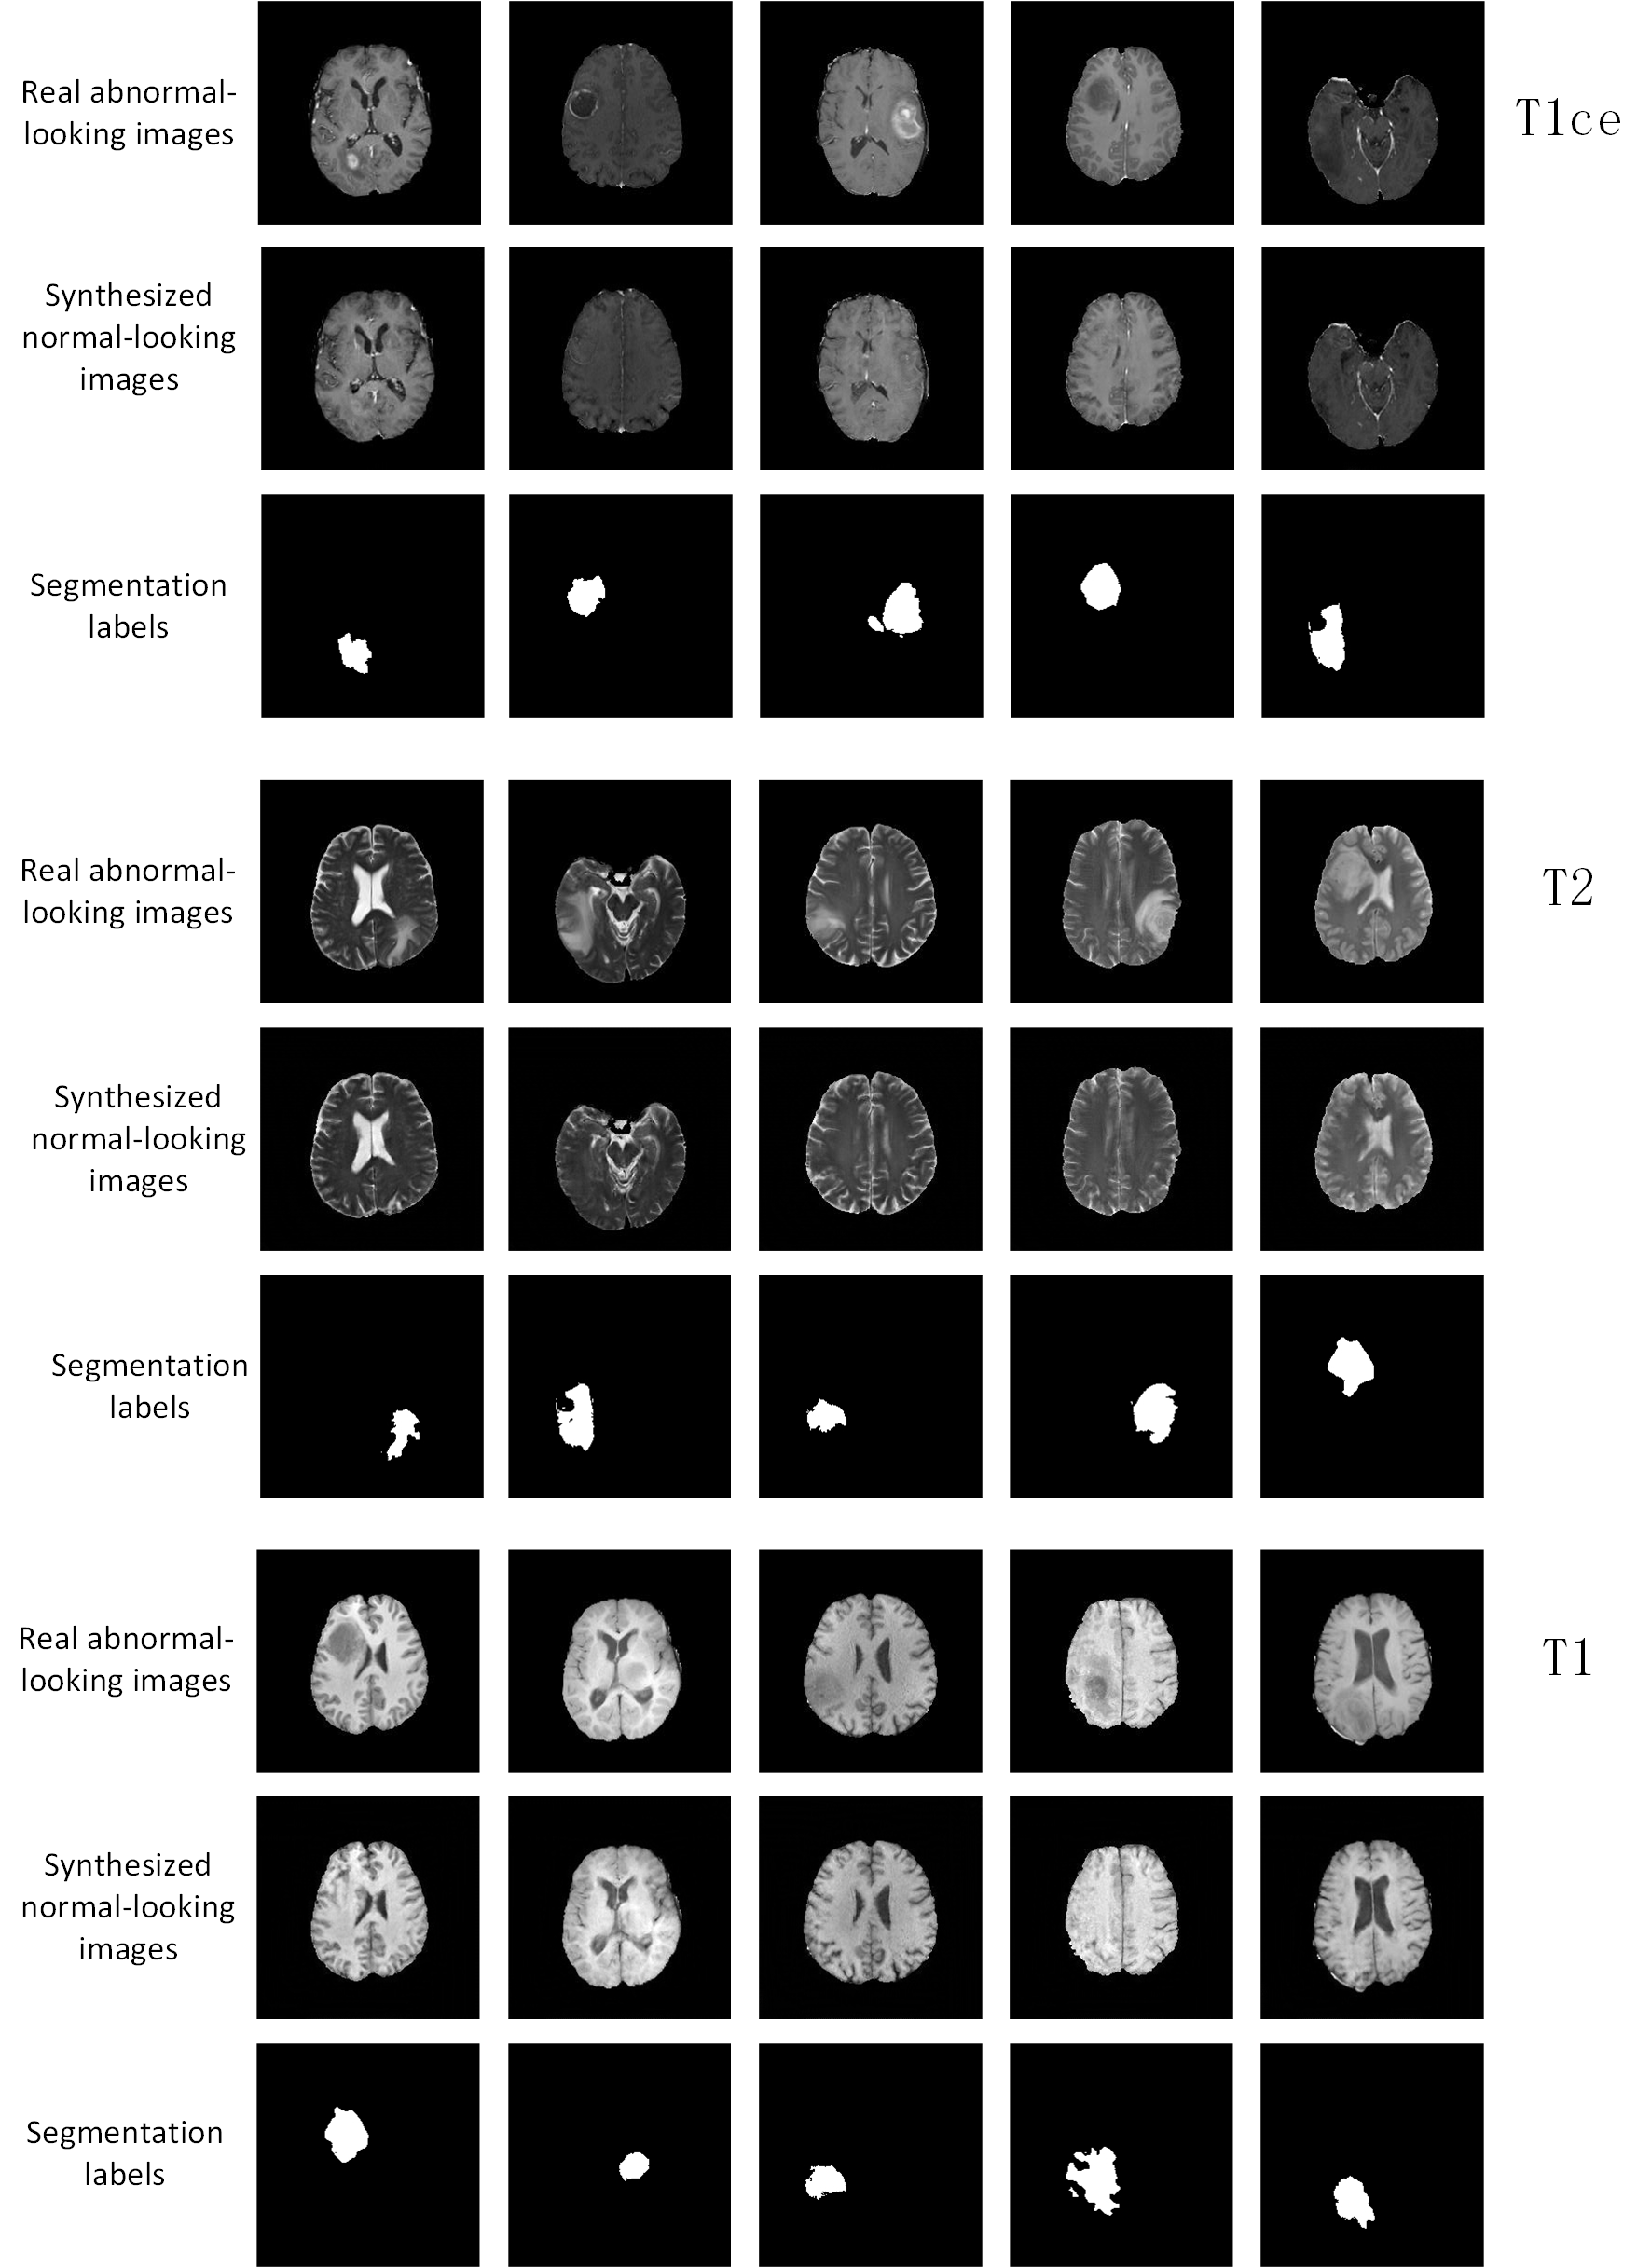

IV-D Results on more MRI modalities with brain tumor.

The ANT-GAN model is mainly evaluated and validated on the FLAIR modality. However, we also test the ANT-GAN model on other three MRI setting including T2, T1ce and T1 modalities. The generated pseudo healthy images are shown in Figure 10.

Refer to caption

Figure 10: More results on the synthesized normal-looking MRI images on T1ce, T2 and T1 modalities.